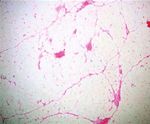

(Figure 6(a)). Additionally, in a few subcapsular areas, there         cally, the encapsulated/noninfiltrative angiolipoma presents

were evident small groups of tiny thin-walled hyperplastic             as a subcutaneous nodule: the lesions are commonly multi-

vascular vessels, most of which exhibited the formation of             ple, typically firm, tender to palpation but often painful,

fibrous thrombi in their lumens (Figure 6(b)). These mor-               and rarely associated with overlying skin changes [2, 5, 9,

phological characteristics were compatible with the diagnosis          10]. Pain and associated neuropathies are secondary to vascular

of angiolipoma [6].                                                    engorgement and edema that can lead to compression of the

Figure 6: Histological examination of the lesion: (a) mature adipose and proliferated vascular tissue (hematoxylin and eosin; magnification

×40); (b) hyperplastic vessels with fibrous thrombi (hematoxylin and eosin; magnification ×100).